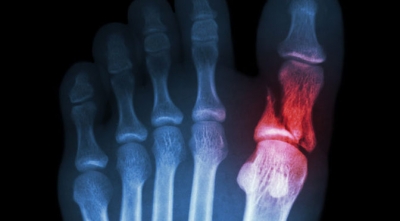

Gout—this form of arthritis occurs when uric acid builds up in the joint and then crystallizes, causing severe pain, inflammation and swelling. Gout most often affects the big toe joint and can be triggered by certain foods, such as shellfish, red meat, organ meats, red wine, brandy, and other alcoholic beverages.

Metabolic—this refers to gout, a form of arthritis that frequently strikes the joint at the base of the big toe. It has to do with the body being unable to rid itself of uric acid. An overabundant amount of this substance will cause crystals in the joints and sudden and extreme pain.

Gout

A specific type of arthritis, gout is caused by having too much uric acid in the blood stream. While this doesn’t cause symptoms in all patients, in certain individuals these high levels of uric acid cause crystals to form on the joints, usually the big toe. Gout manifests in sudden attacks of pain in the big toe until it is treated. Risk factors for gout include being overweight and having a diet high in meat and alcohol.

Gout is usually somewhat obvious by its visible effects on the big toe, causing swelling and redness. Steroids can stop a sudden gout attack, and there are long-term treatment options as well for chronic gout.